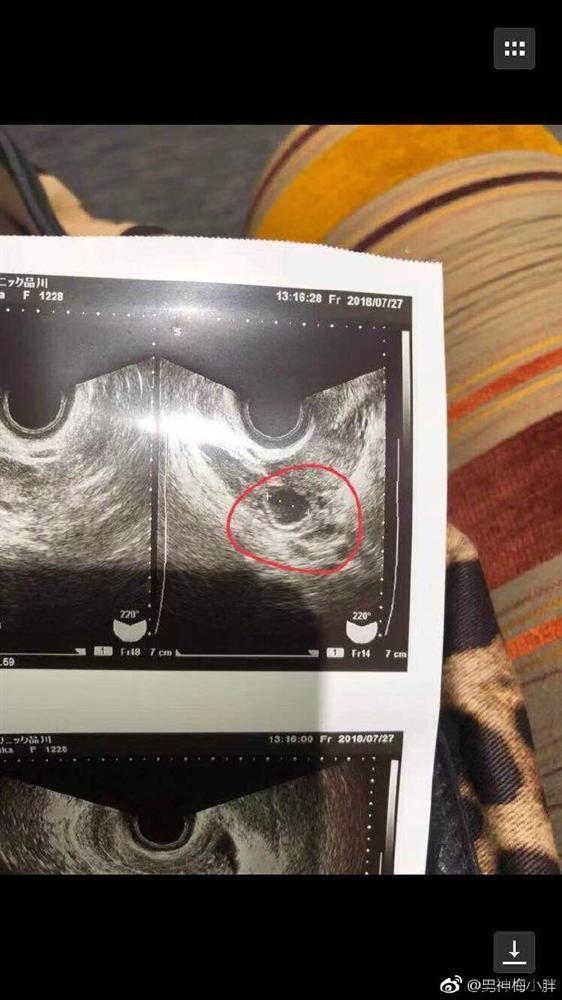

Tưởng Kình Phu hết sức chăm sóc và yêu thương bạn gái, toàn tâm toàn ý với cô. Tuy nhiên cô gái này sau một thời gian yêu đương liền lộ bản chất thật, thường xuyên đi bar, qua đêm bên ngoài, có những mối quan hệ không rõ ràng đồng thời từng giả mang thai để lừa Tưởng Kình Phu.

Hình ảnh được cho là phía nhà gái giả mang thai

Thậm chí khi biết tin bạn gái mang thai, Tưởng Kình Phu đã lên kế hoạch mua nhà và làm visa cho cha mẹ tới Trung Quốc. Tuy nhiên, Mai Tiểu Bán không nói rõ cụ thể lý do vì sao cặp đôi xảy ra xô xát. Ngoài ra, phía nhà gái còn cấu kết với xã hội đen uy hiếp Tưởng Kình Phu và đòi chi trả 1 tỷ yên (tương đương 206 tỷ đồng).

Sau loạt thông tin Mai Tiểu Bán tiết lộ trên mạng, Haruka Nakaura lập tức phản pháo toàn bộ là sai sự thật. Cô khẳng định bản thân từng mang thai nhưng bị Tưởng Kình Phu hành hung, đánh vào bụng dẫn đến mất con. Hiện tại cô cùng gia đình cố liên lạc với Tưởng Kình Phu nhưng đều không được.